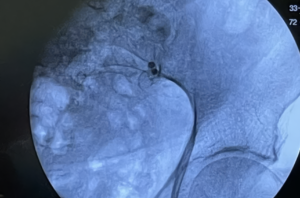

Dr. Quang Nguyen utilizes iFuse INTRA X® allografts for the percutaneous treatment of an active male golfer's SI joint dysfunction.